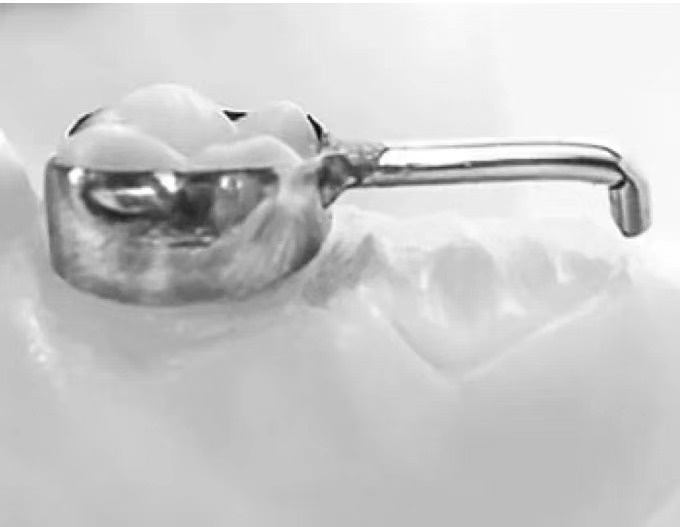

远中导板式间隙保持器

适用于第二乳磨牙早失、第一恒磨牙尚未萌出或萌出中。